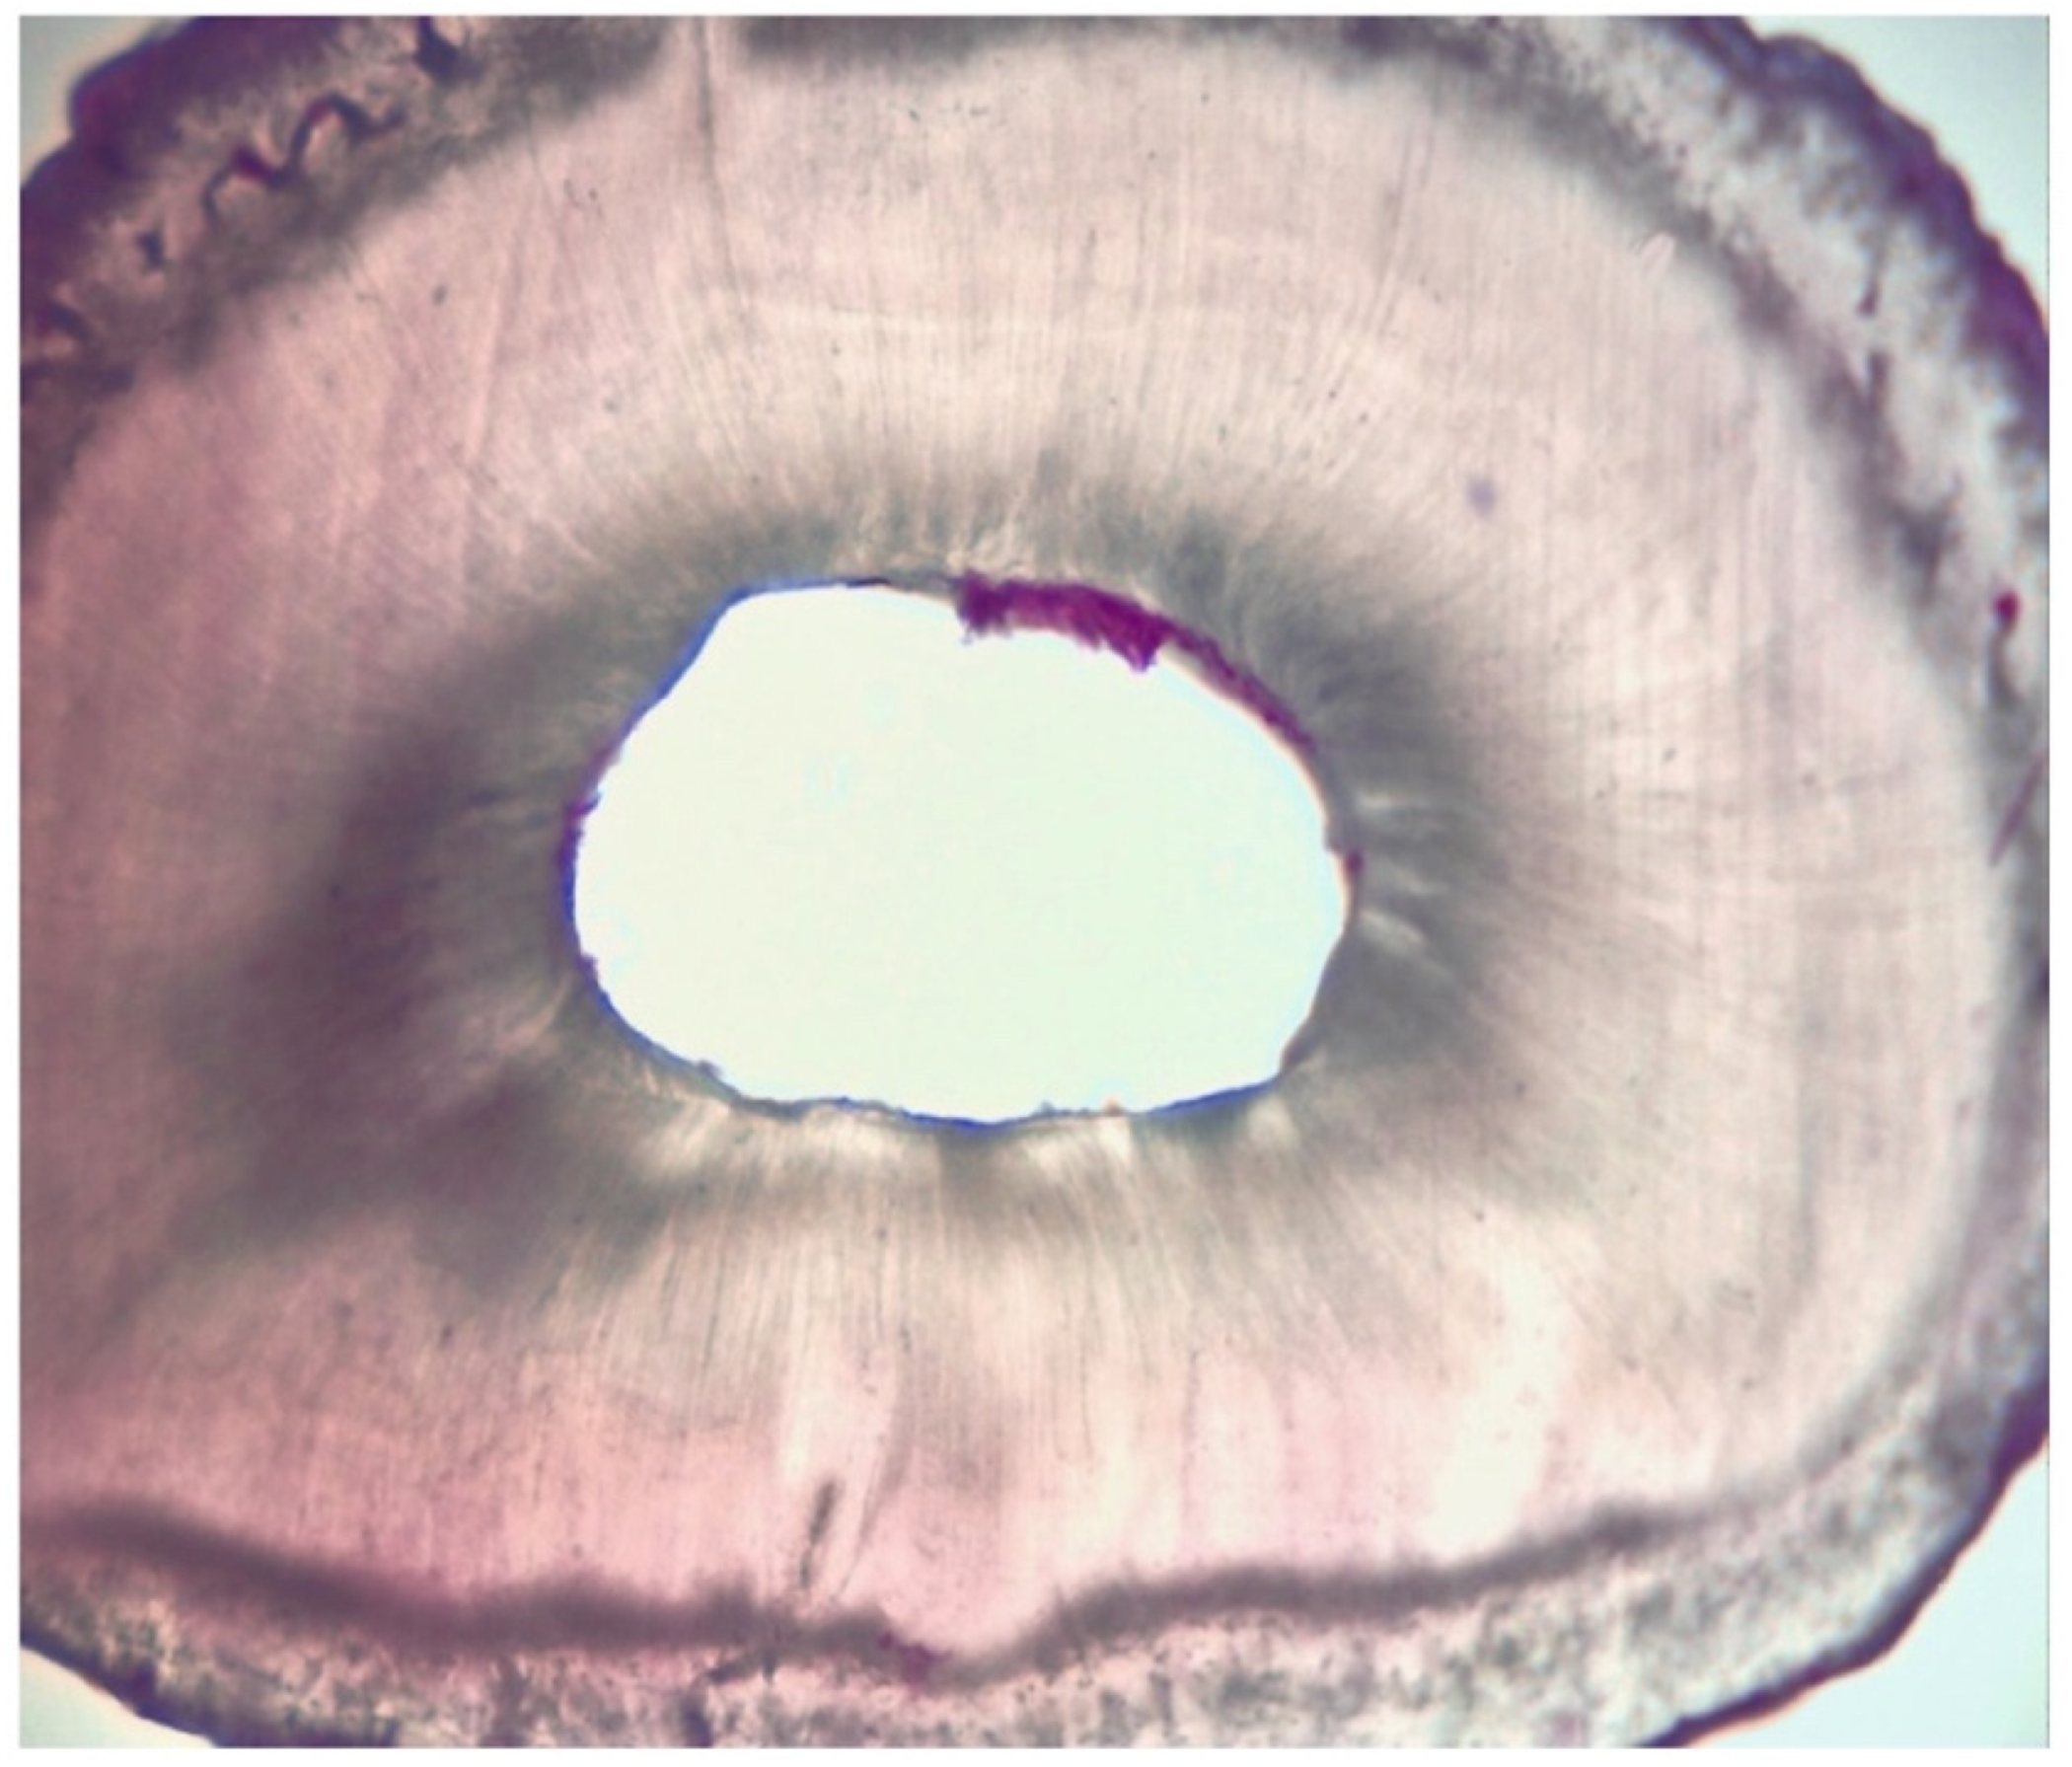

2.3. Assessment of Root Canal Cleanliness

| Grading | |

|---|---|

| I | presence of debris within the area |

| II | presence of debris in more than 50% of the entire area |

| III | presence of debris in more than 25% of the entire area |

| IV | absence of debris or presence of debris in less than 25% of the entire area |